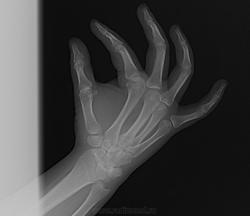

Девушка 16 лет, упала, беспокоит дискомфорт в области запястно-пястных суставов. В прошлом перелом "кисти" как она сказала, а что именно не помнит (по снимкам, полагаю, был перелом луча). Не нравится мне соотношение в л/з суставе. Есть ли подвывих какой?

Полулунная кость очень подозрительна. А более боковой проекции нет?

А про дискомфорт не ошиблись - то есть ладошка чешется, да?.. Снимки интересные - с подвыподвертом каждый немного.) Но тем не менее, всё при нём... на каждом. Возможно был перелом луча, а может, его строение аномальное слегка. Без архивных и бокового не заключал бы я перелома!.. И вывиха тоже.)

Перелом головки 4-й пястной кости. Согласен с Максималистом о необходимости снимка в боковой проекции.

Перелома тоже не вижу.

Я, может быть тоже не вижу ,а только предполагаю. Поэтому предложил боковую проекцию.

По данному случаю мне кажется перерыв кортикального слоя по контуру со стороны локтя.